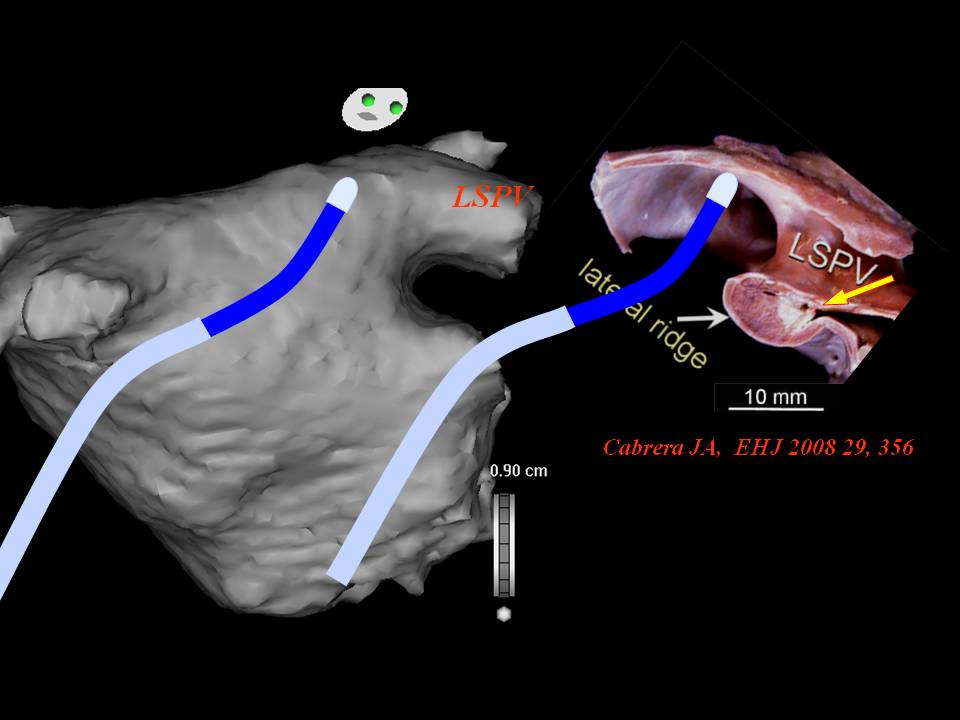

肺静脉隔离术难点

董建增